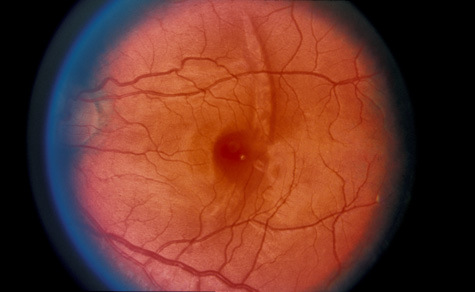

Commotio retinae (Latin, meaning retinal contusion) is a contrecoup injury. It can occur peripherally (Fig. 8) or centrally, in which case it is called Berlin's edema (Fig. 9). Immediately and for several hours after the trauma, the retina appears normal, although the patient may complain of decreased vision. Thereafter, the outer layers of affected retina become opaque. On fluorescein angiography, the opaque retina blocks background choroidal fluorescence, and in most cases there is no leakage into or under the retina (Fig. 10). For years, clinicians had difficulty explaining this blockage, because leakage is expected in conditions with edema. It was then shown in experimental animals and in human autopsy eyes that Berlin's edema is not true edema. The retinal opaqueness is the result of intracellular edema and fragmentation of the photoreceptor outer segments and intracellular edema of the underlying pigment epithelium. There is little or no intercellular fluid.66–69

Fig. 9. Commotio retinae in the macula (Berlin's edema). The visual acuity was 20/25 at the time of the photograph and later improved to 20/15.